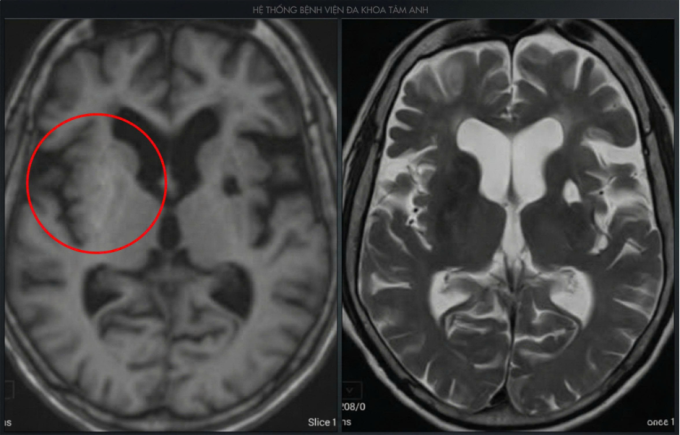

Xét nghiệm đường máu lúc nhập viện là 341 mg/dl, cao hơn gần 3-5 lần so với ngưỡng bình thường. Chỉ số HbA1c - đường huyết trung bình ba tháng 14,59%, cho thấy tình trạng tăng đường huyết kéo dài trong nhiều tháng. Kết quả chụp MRI 3 Tesla não ghi nhận tổn thương hạch nền hai bên, chủ yếu tại bèo sẫm bên phải - nguyên nhân gây rối loạn vận động kiểu múa vung (hemiballismus) do rối loạn chuyển hóa khi tăng đường huyết.